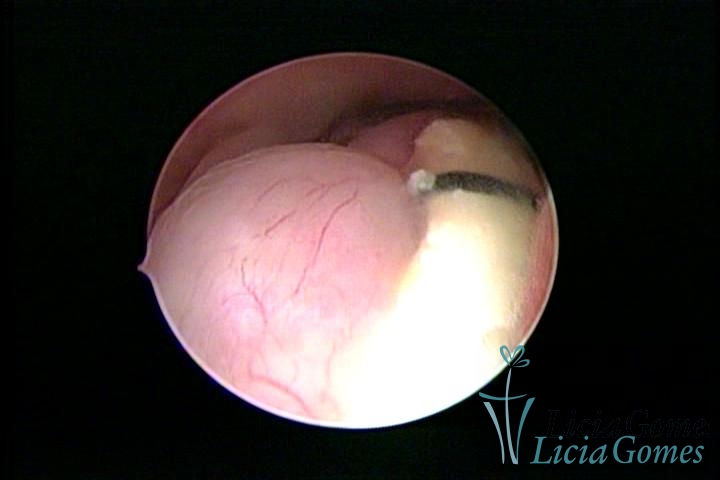

Canal cervical trófico, com o fio de Mirena®